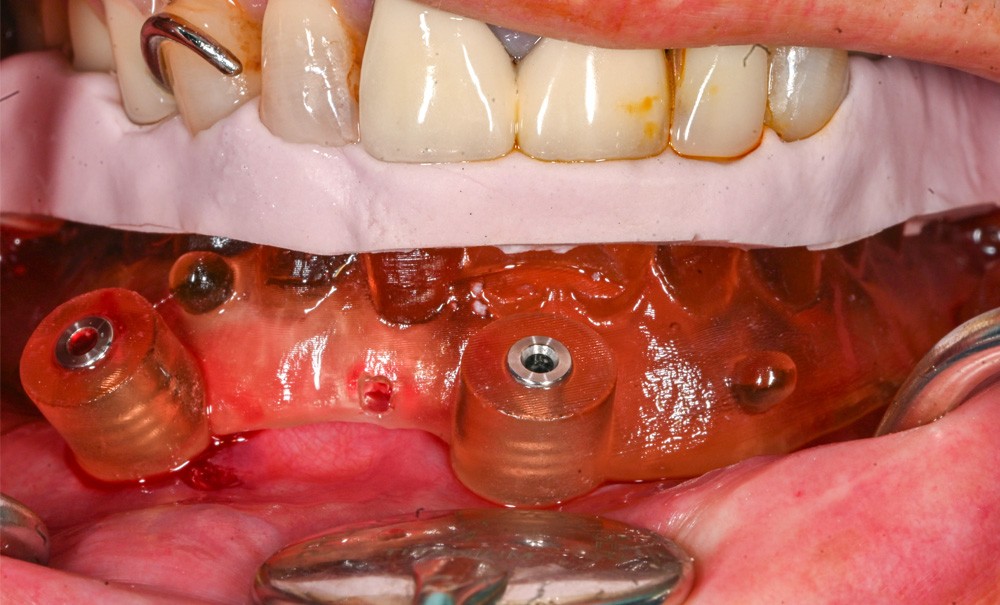

Gestion du nerf incisif lors de la pose de deux implants symphysaires : cas clinique

L’utilisation de deux implants symphysaires associés à des attachements afin de stabiliser une prothèse amovible complète est une solution thérapeutique validée par de nombreuses publications. Le consensus de McGill, publié en 2002, rapporte qu’une prothèse mandibulaire stabilisée par deux implants inter-foraminaux serait le traitement de référence pour un édentement complet mandibulaire [1]. Ce consensus a été étayé par la conférence d’York en 2009 et souligne l’amélioration significative de la satisfaction, du confort et de la rétention prothétique obtenue grâce aux attachements supra-implantaires, tout en maintenant un rapport coût/bénéfice favorable [2]. Ce protocole demeure ainsi la référence dans de nombreuses situations cliniques d’édentement total mandibulaire avec un taux de survie implantaire à 10 ans proche de 95 % [3].

La zone inter-foraminale est traditionnellement considérée comme anatomiquement sûre, car éloignée du trajet principal du nerf alvéolaire inférieur. De nombreuses variations anatomiques représentent toutefois un risque neurovasculaire non négligeable, souvent sous-estimé lors de la planification chirurgicale. La symphyse mentonnière est le carrefour de différents rameaux vasculaires qui peuvent être plus ou moins bien visualisés sur une imagerie CBCT, comme le canal lingual. Sur le plan nerveux, l’anatomie du foramen mentonnier présente différentes formes. Il peut être multiple et présenter une courbure plus ou moins prononcée. Dans une revue systématique avec méta-analyse, Muinelo-Lorenzo et al. rapportent une prévalence des foramina mentonniers accessoires chez environ 8 % des sujets, avec une forte dominance unilatérale (plus de 80 % des cas) et une localisation parfois supérieure au foramen mentonnier principal [4].

La présence d’un canal incisif antérieur, prolongement terminal du canal mandibulaire, est également un obstacle anatomique pour toute chirurgie dans cette région. Le canal incisif mandibulaire abrite la branche incisive du nerf alvéolaire inférieur et ses éléments vasculaires associés. La prévalence moyenne rapportée quant à sa présence est d’environ 90 % avec un diamètre variant de 0,4 à 4,1 mm et une longueur de 6,6 à 40,3 mm [5]. Ce canal, de trajectoire variable, peut se situer à une distance réduite de la corticale vestibulaire et de la crête alvéolaire, exposant ainsi le patient à des complications sensitives en cas d’atteinte lors de la pose d’implants dans cette région. Les atteintes du nerf incisif peuvent se manifester par des paresthésies, des douleurs ou des dysesthésies, source d’inconfort pour le patient. Il est à noter que l’identification du nerf incisif mandibulaire tend à diminuer vers la symphyse.